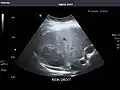

Kidneys: Right and left kidneys measure 11.5 cm and 12 cm in length respectively. No hydronephrosis. Small left lower pole kidney cyst.

Right kidney